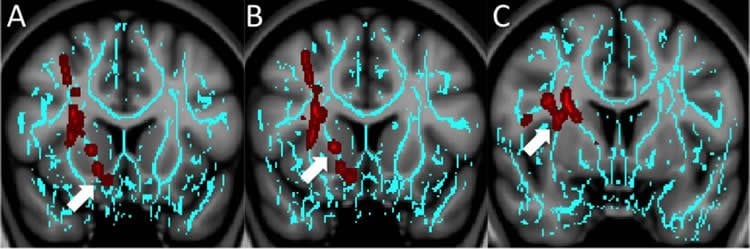

The researchers saw unique white matter injury patterns in the patients who had depression or anxiety. Compared to controls, patients with depression had decreased fractional anisotropy (FA), a measure of the structural integrity of white matter connections, around an area near the deep gray matter of the brain that is strongly associated with the brain’s reward circuit.

Anxiety patients had diminished FA in a part of the brain called the vermis that helps modulate fear-related behaviors. Since the vermis has not been associated with dysfunction in non-traumatic anxiety disorders, this finding may indicate that different treatment targets are required for patients with anxiety after trauma, the researchers said.

No regions of significantly decreased FA were seen in patients with irritability relative to the control subjects.

Compared with control subjects, patients with mTBI and depression had decreased fractional anisotropy in the superior longitudinal fasciculus (P = .006), white matter around the nucleus accumbens (P = .03), and anterior limb of the internal capsule (P = .02). Patients with anxiety had diminished fractional anisotropy in the vermis (P = .04). No regions of significantly decreased fractional anisotropy were seen in patients with irritability relative to control subjects. Injury in the region of the nucleus accumbens inversely correlated with recovery time in patients with depression (r = −0.480, P = .005).

Unique white matter injury patterns were seen for two major posttraumatic neuropsychiatric symptoms. Injury to the cerebellar vermis in patients with mTBI and anxiety may indicate underlying dysfunction in primitive fear conditioning circuits in the cerebellum. Involvement of the nucleus accumbens in depression after mTBI may suggest an underlying dysfunctional reward circuit that affects the prognosis in these patients.